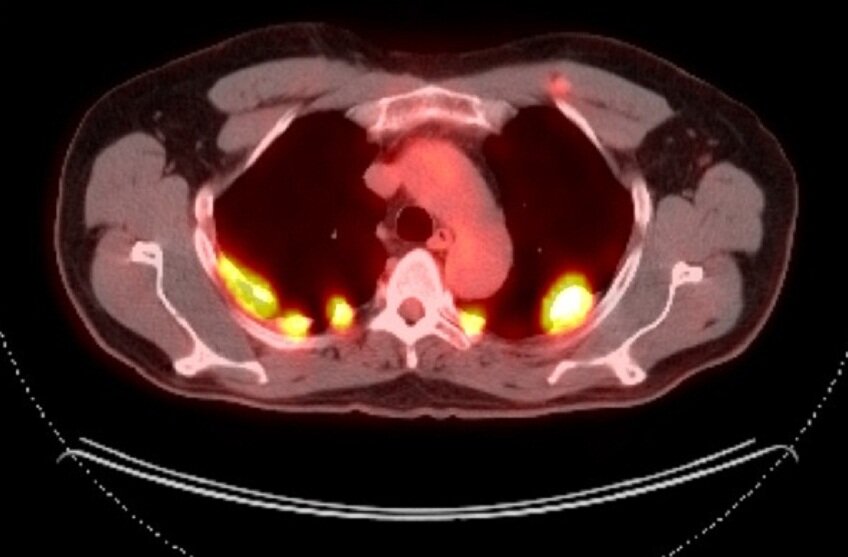

При подозрении на метастатический рак легкого наиболее информативным методом оценки распространенности заболевания является ПЭТ-КТ, поскольку в сравнении с компьютерной томографией позволяет более достоверно оценить состояние лимфоузлов, а также выявить метастатические очаги в других органах.

Снимок пораженного легкого, ПЭТ-КТ.